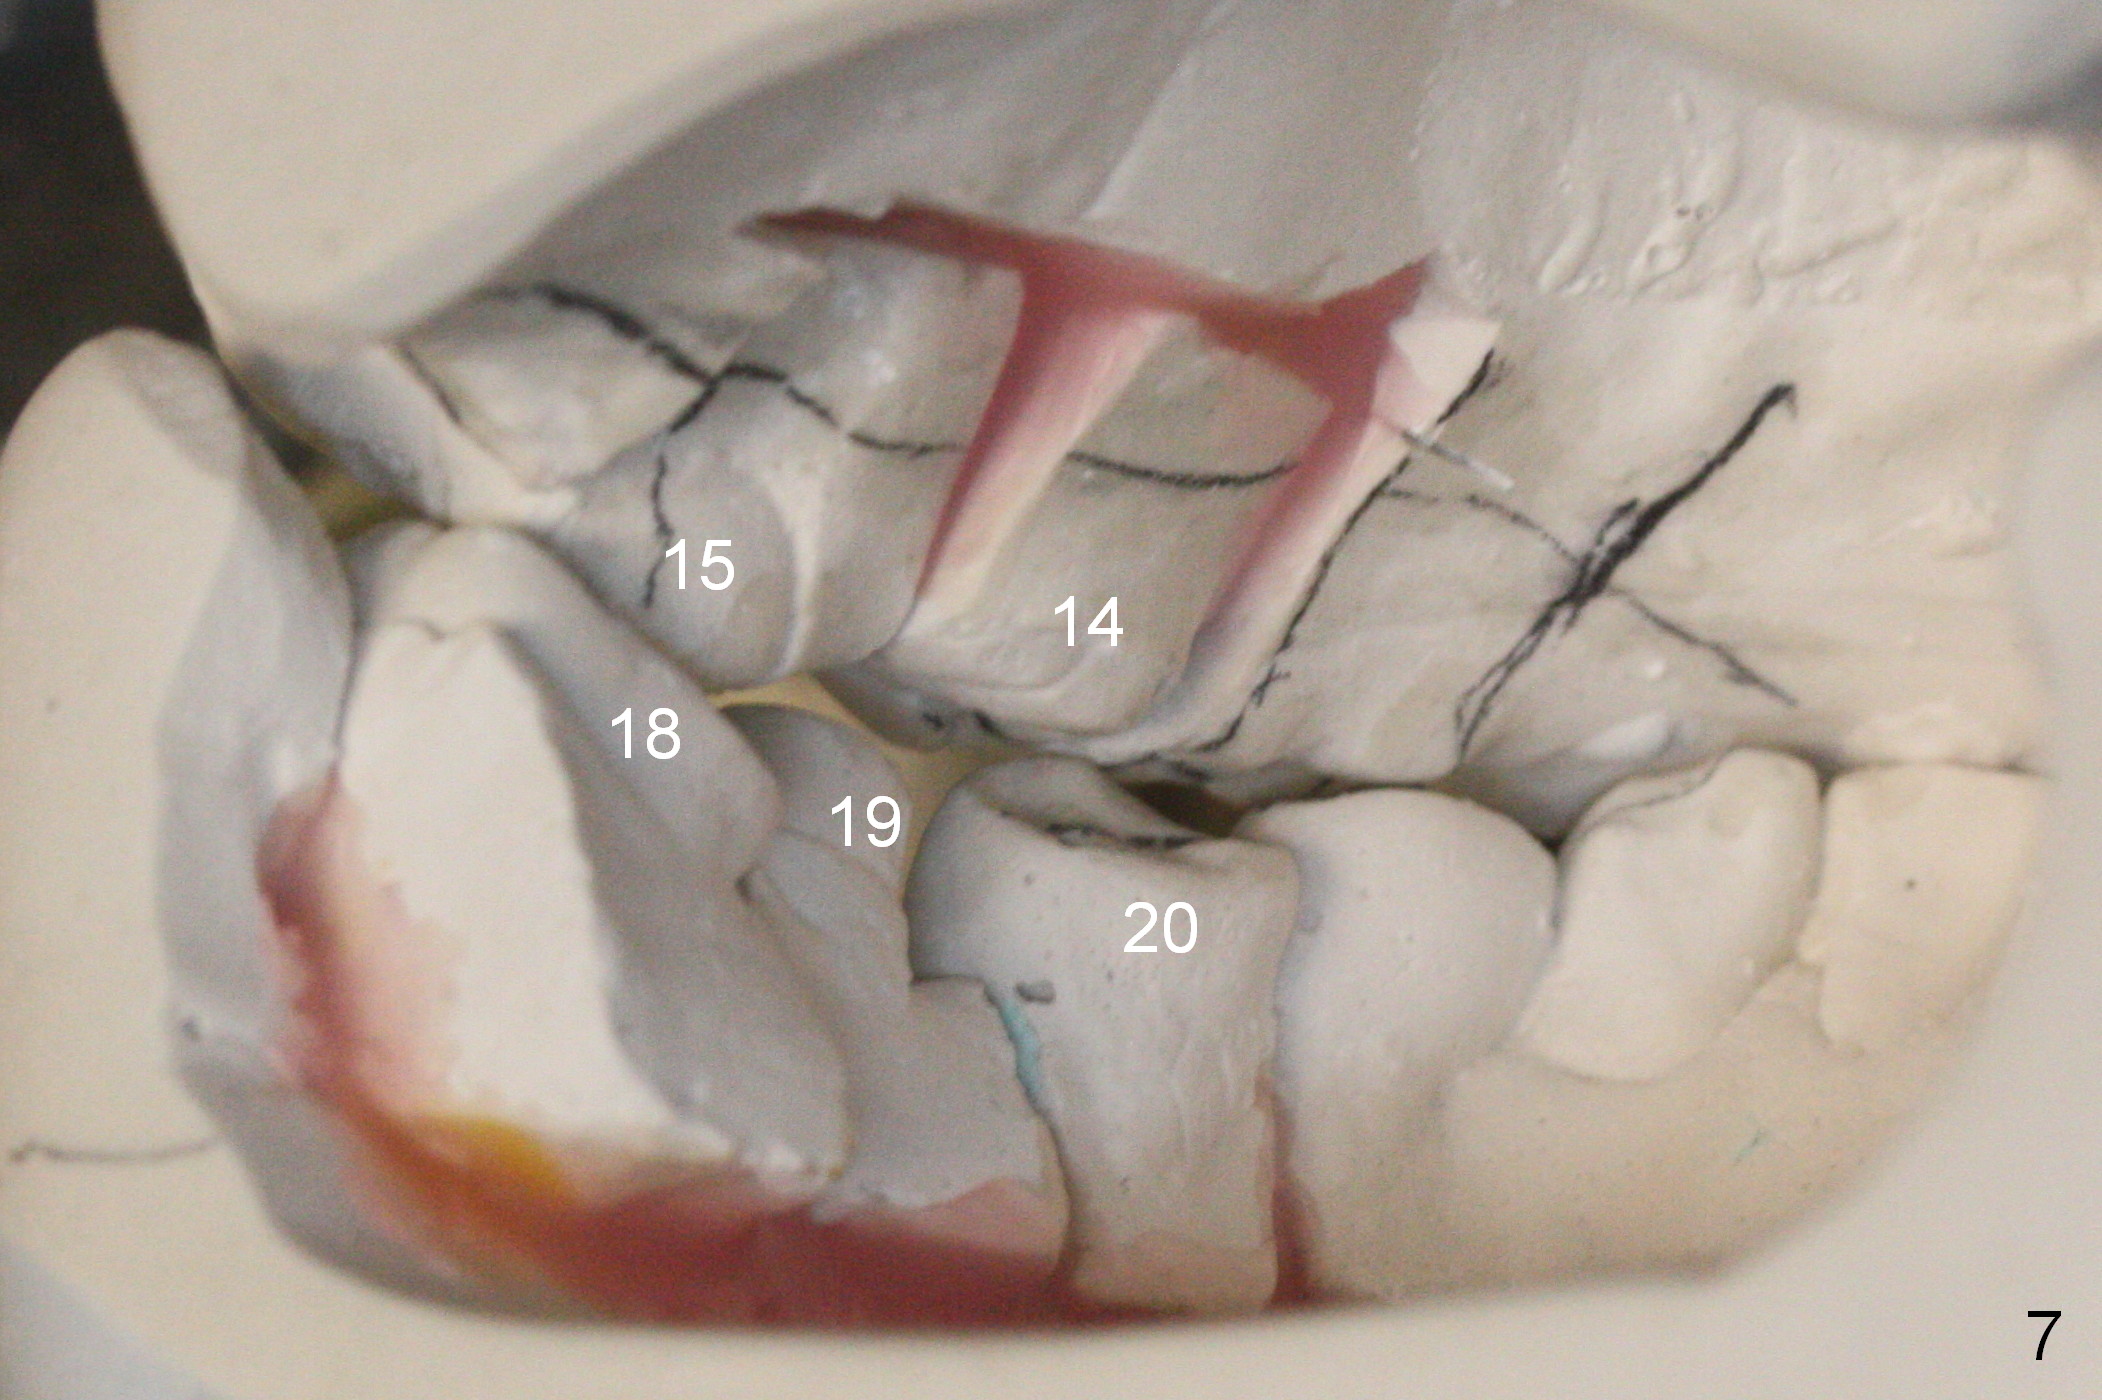

A 40-year-old man had automobile-related mandibular fracture and surgical reduction several years ago. Since then there has been cross bite in the left molar region (Fig.1-2) with abnormal wear facets in the occlusal surface of the teeth #14, 15 and 18 (Fig.3,4 *). At the time of implant placement at #19, the patient reports tooth sensitivity at #15 and wonders whether increase in the occlusal surface of the future crown at #19 can alleviate the tooth sensitivity or not. In fact the tooth #14 and 19 were in cross bite when the sites of #20 and 21 were processed for implant crowns (Fig.1). The cross bite of the left molar area appears to be so severe that surgical segmental osteotomy or orthodontic treatment is required (Fig.5-7).

In the lower arch, the buccal surface of the crowns at #20 and 21 is reduced substantially so that the crowns functions as lingual anchorage. The abutment at #19 will be changed to an angled one; in the same way, the temporary crown at #19 is lingually positioned. With full arch brackets and bands, the tooth #18 is expected to be lingualized (Fig.6 arrows). Elastics can be placed between the left upper and lower molars (from upper lingual to lower buccal) to facilitate mutual shifting.